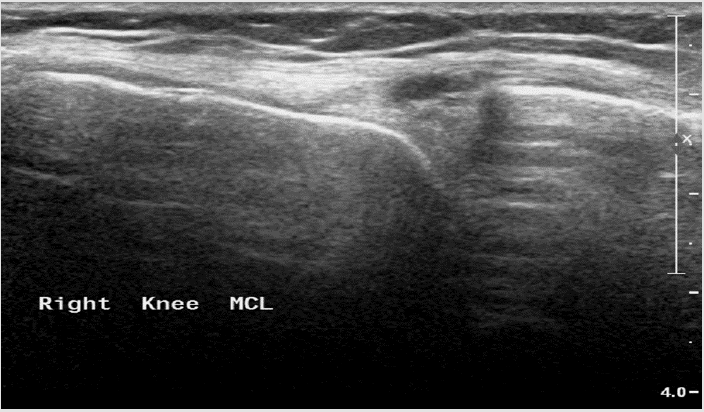

Figure 11: Medial collateral ligament partial tear - thickening, hypoechoic proximal part of the ligament with fluid around it.